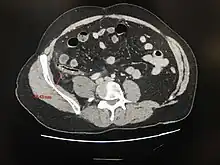

- le scanner abdominal peut montrer un aspect de masse de la fosse iliaque droite. Cet examen tend à se généraliser en raison d'une très bonne fiabilité[55] Ailleurs, le scanner peut aider au diagnostic différentiel (tumeur cæcale, iléite terminale, maladie de Crohn, adénite mésentérique, etc.) ;

Appendicite aiguë perforée

Scanner abdominal : distension de l'appendice, infiltration de la graisse péri appendiculaire, pneumopéritoine localisé - l'IRM abdominale est également très fiable pour le diagnostic[56].